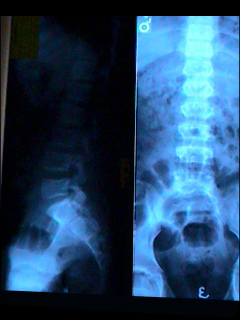

Lumbosacral spine X-ray